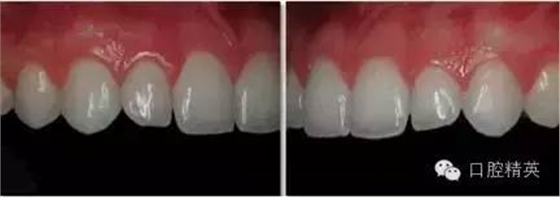

上前牙照

正面观

1:1 (1:1.5)放大倍率

需要使用拉钩

•上前牙应位于照片中央,用中线及唇系带作为参照点平分照片。人中在此视角中应无法暴露。

•照片的中线应水平平分中切牙(请勿使用切平面作为水平中线)。

•拉钩不应出现在此图中。照片中的龈缘应清晰可见。

•下颌牙不应出现在此视角中。

•可以使用背板拍照。如使用背板,应避免出现阴影。

•在患者的正前方拍照,相机应与被拍摄物成90°。

•在1:1 (1:1.5)视图中,只能拍到4~6颗牙齿。

侧面观

•侧切牙应位于照片中央,纵向平分照片。

•照片的中线应水平平分侧切牙(请勿使用切平面作为水平中线)。

•相机应与侧切牙唇面成90°角放置。

•近相机处的拉钩应尽量向后牙区域牵拉,远相机处的拉钩应尽量向远离牙齿的方向牵拉。